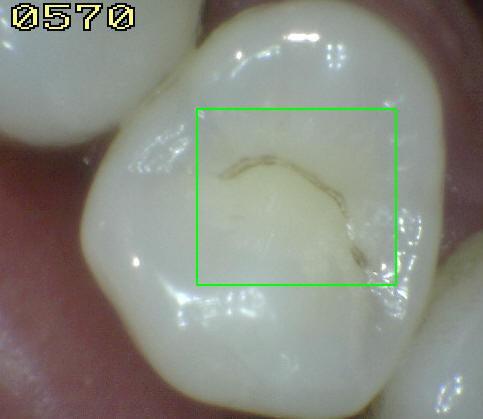

2. PERDIDA DE LA INTEGRIDAD DE LA SUPERFICIE

1. HALLAZGO: macha café con presencia de cavidad

1. CRITERIO DE DIAGNOSTICO: despues de secar por 5 sg, existe una pérdida de integridad superficial sin exposición de dentina

1. DIAGNOSTICO

1. ICDAS 3

2. TRATAMIENTO

1. operatoria

2. ACTIVIDAD

1. activa/detenida